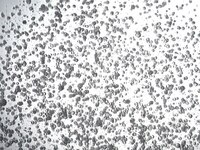

SCC741 Sigma-Aldrich3dGRO™ Colorectal Organoids (CSC.413)

Overview

| Material Size | ≥ 1500 organoids/vial |